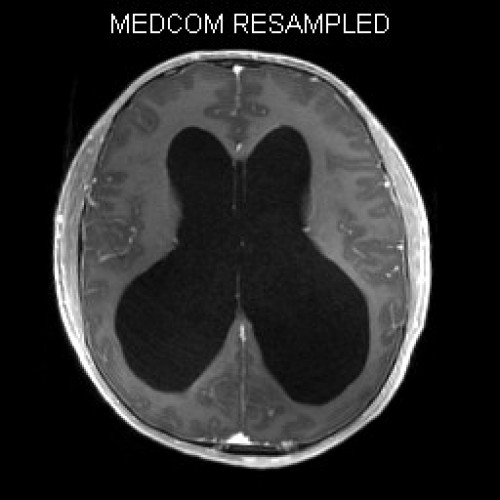

ICD: C75.3

ICD: G91.9

12-jähriger Junge. Die Eltern werden zu einem Gespräch bei der Klassenlehrerin gebeten, weil ihr Sohn sehr unaufmerksam geworden sei und seine Leistungen in der Schule bedenklich abgenommen hätten. Er droht das Klassenziel der 6. Klasse nicht zu erreichen.

Den Eltern war seit längerer Zeit bereits aufgefallen, dass sich ihr Sohn nach der Schule am liebsten ins Bett lege, um für eine Stunde einen Mittagsschlaf zu halten.